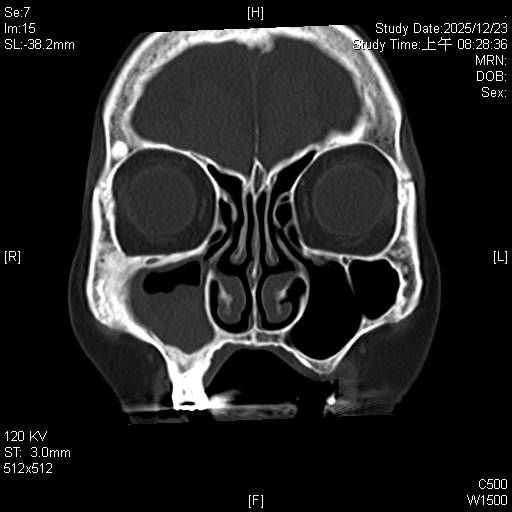

東元綜合醫院耳鼻喉科詹健暘主治醫師表示,阿嬤經過診斷為「慢性鼻竇炎,伴隨黴菌性鼻竇炎(fungal sinusitis)」。這類疾病在台灣潮濕的氣候環境下相當常見,黴菌塊(或稱黴菌球)常堆積在單側上頜竇,屬於非侵襲性黴菌感染,但在鼻竇內會不斷堆積成團塊,典型的表現為單側或局部鼻竇阻塞、鼻涕倒流,甚至頭痛。

考量高齡病人,手術治療面臨最大的挑戰在於「麻醉風險」。90歲長輩通常伴隨心血管或肺部功能退化,全身麻醉後的甦醒及併發症風險較高。所以經詳細評估後,決定採取局部麻醉下的「鼻竇內視鏡微創手術(functional endoscopic sinus surgery, FESS)」來治療。

耳鼻喉科詹健暘醫師指出,黴菌性鼻竇炎的「黃金標準治療」是透過手術徹底清除黴菌團塊及發炎組織,恢復鼻竇通氣與引流。若單純使用藥物治療,往往難以根治,且長期鼻涕倒流可能引發慢性咳嗽或影響呼吸道健康。